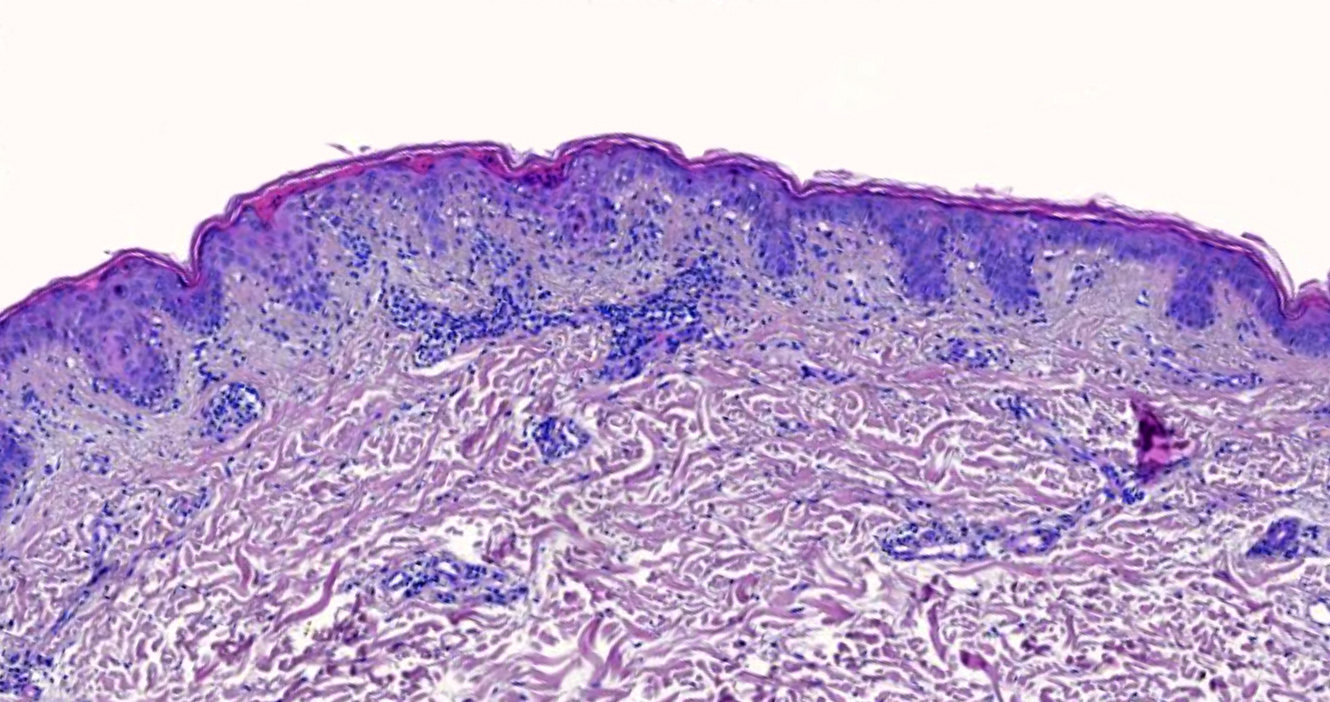

Microscopic (histologic) description

- Interface dermatitis with variable degrees of basal layer vacuolization and scattered cytoid bodies (Lupus 2012;21:577)

- Occasionally, basal layer vacuolation and keratinocyte apoptosis may be so severe that full thickness epidermal necrosis may result, generating a differential diagnosis of erythema multiforme

- Erythema multiforme-like lesions may occur, showing exuberant interface tissue reaction (Rowell syndrome)

- Dyskeratotic keratinocytes extending into upper spinous layers is a very characteristic but rare finding of SCLE (J Cutan Pathol 2001;28:1)

- Hyperkeratosis / parakeratosis may be present

- Sometimes focal hypergranulosis

- Superficial and sometimes superficial and deep perivascular lymphocytic infiltrate (Dermatol Ther (Heidelb) 2021;11:131)

- Periadnexal mononuclear cell infiltrate may be present (Dermatol Ther 2021;11:131)

- Dermal mucin, which may be highlighted with Alcian blue or colloidal iron

- Compared with idiopathic SCLE, drug induced variants are more commonly associated with leukocytoclastic vasculitis and have less mucin deposition (J Am Acad Dermatol 2019;81:403)

- Epidermal atrophy, follicular plugging, basement membrane thickening, dermal mucin and pigment incontinence may be present but less prominent than in chronic lupus erythematosus

Microscopic (histologic) images

A 35 year old woman presents with multiple nonscarring erythematous annular plaques that arise in photo exposed areas 8 weeks after introducing terbinafine for treatment of onychomycosis. A biopsy of one of the lesions was performed (shown above). What is the most likely diagnosis?

Board review style question #2

A 50 year old man with a history of recent onset hypertension treated with enalapril presented with a 1 month history of annular and erythematous polycyclic plaques with peripheral scale that were located in sun exposed areas. No other systemic manifestations were found. Serologic test results were positive for ANA, anti-Ro / SSA and anti-La / SSB, while negative for ds-DNA, anti-histone and anti-Smith. Which histopathological finding that can be seen in this image is more characteristic of the patient's clinical type?